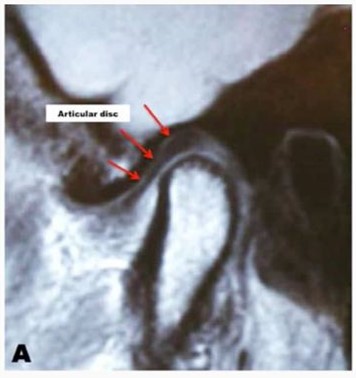

Тут мыщелок в норме (Фото от Larry M.Wolford, DMD)

...а тут диск смещён вперёд (по-научному это называется «вентральная дислокация диска»)